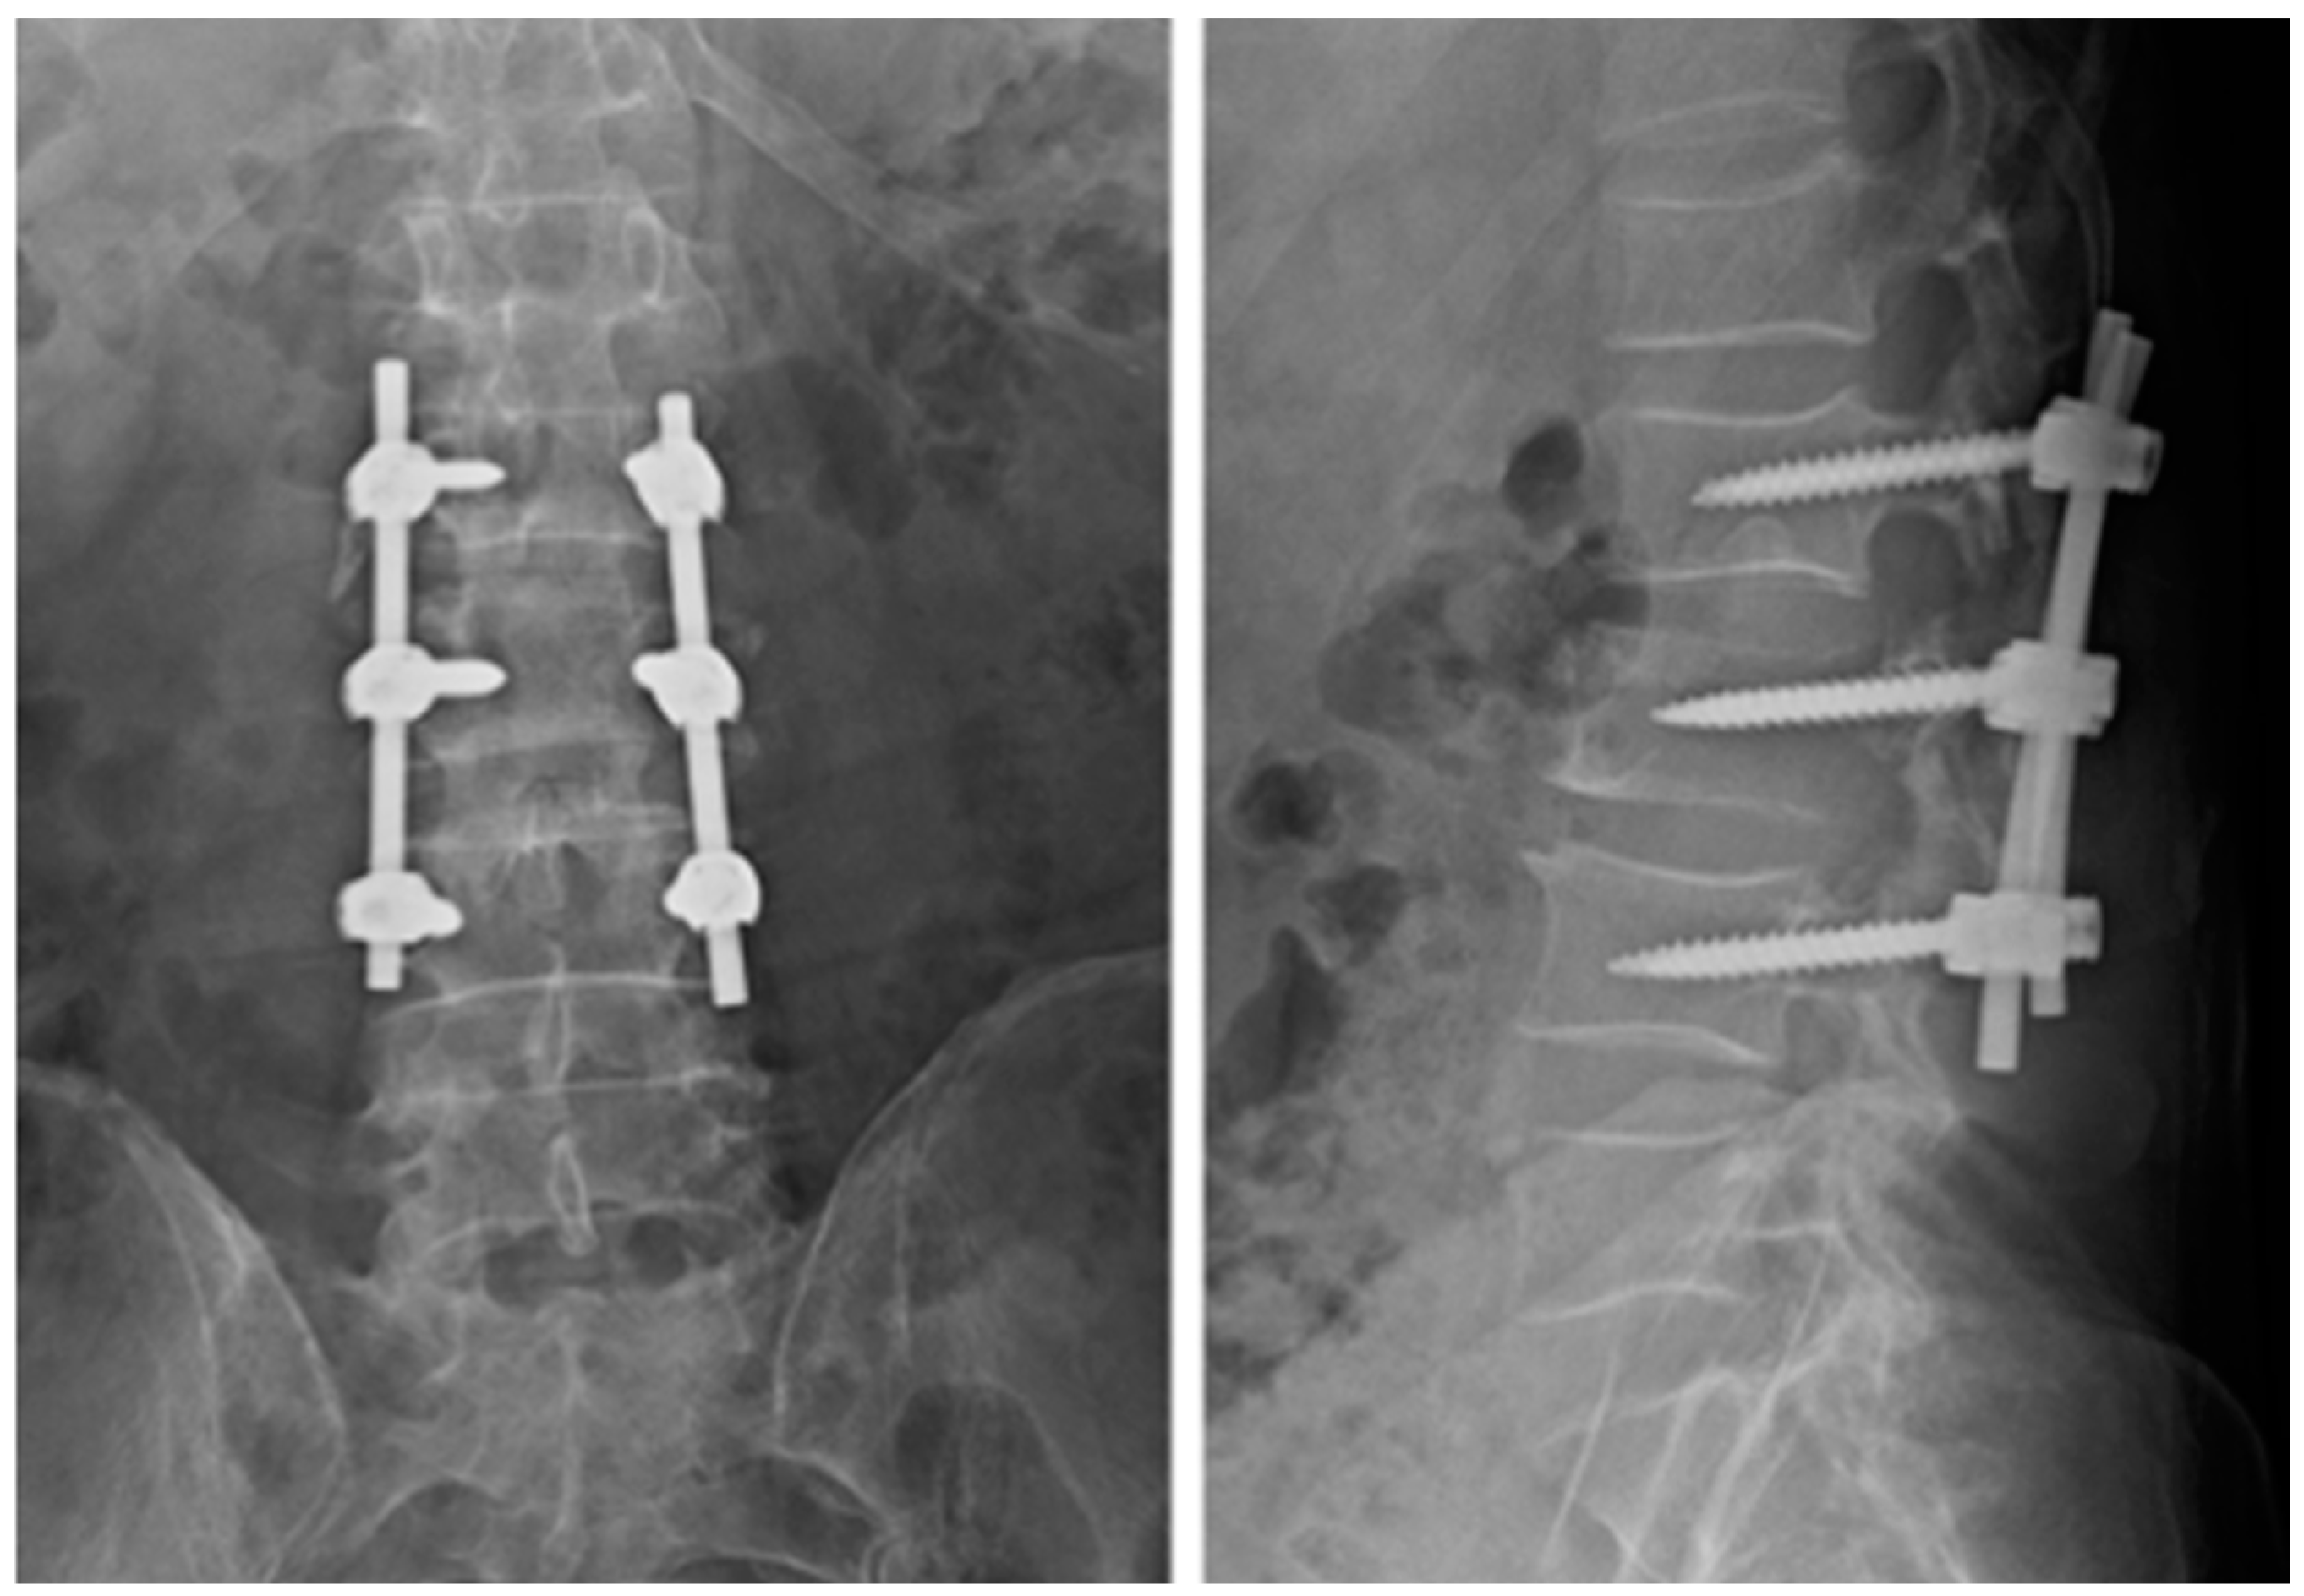

| [12] (2015) | Case report | 1 | Melanoma | Lumbar | Surgical procedure: Hemilaminectomy | Pain relief Good MRI response |

| [16] (2018) | Case reports | 2 | N/A | Lumbar Thoracic | Minimally invasive: Transpedicular Approach | N/A |

| [17] (2019) | Case reports | 2 | Breast carcinoma; Lung carcinoma | Lumbar | Percutaneous CT guided (pedicles\vertebral body) | Pain relief Good MRI response |

| [18] (2023) | Case series | 40 | Thyroid carcinoma; Lung carcinoma; Sarcoma; Others (*) | Cervical Lumbar Thoracic | Percutaneous CT guided (pedicles\vertebral body) | Pain relief Neurological improvement Good MRI response |

| Present study | Case series | 3 | Myxofibrosarcoma; Squamous cell carcinoma of skin; leiomyosarcoma | Lumbar | Transpedicular approach during surgical procedure | Pain relief and neurological improvement ** |